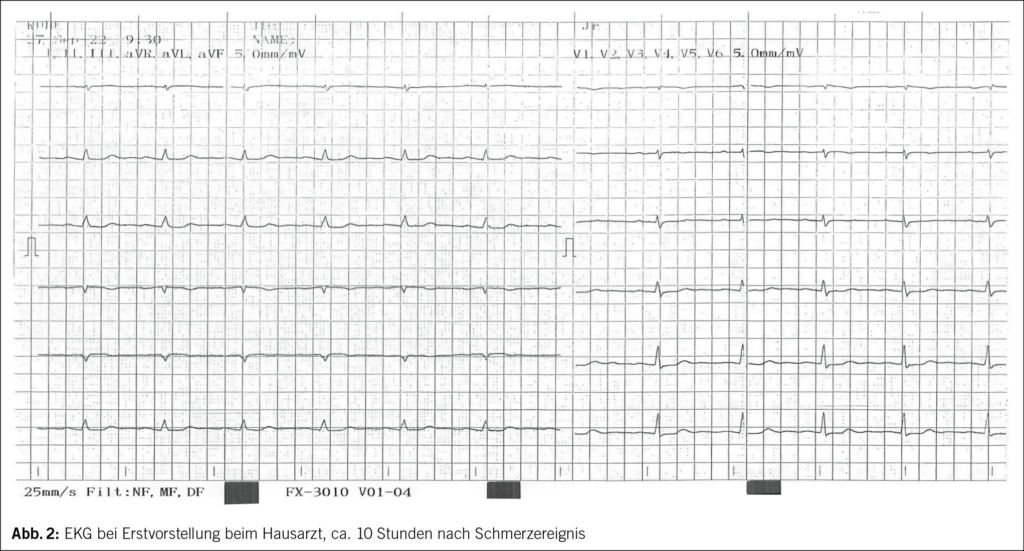

Etwa eine Stunde nach dem Ereignis verspürte die 71-jährige Frau starke Schmerzen in der Brust und zwischen den Schulterblättern, welche nach 1–2 Stunden spontan rückgängig waren. Am Folgetag suchte die Patientin ihren Hausarzt auf, wo ein erhöhtes Troponin Tn-I und anterolaterale sowie inferiore Repolarisationsstörungen mit ST-Senkungen, T-Abflachungen und -Negativierungen im EKG festgestellt wurden (Abb. 2–4).

Das Krankheitsbild des Takotsubo-Syndroms ist durch typische Beschwerden ähnlich eines akuten Koronarsyndroms mit akuten thorakalen Schmerzen, Dyspnoe sowie erhöhten kardialen Biomarkern gekennzeichnet. Elektrokardiographisch zeigen sich typischerweise ST-Strecken-Abnormalitäten, am häufigsten initial ST-Hebungen und im Verlauf fortschreitende T-Inversionen und QT-Zeit-Verlängerungen (2, 3). Echokardiographisch und in der Ventrikulographie sind typische regionale Wandbewegungsstörungen sichtbar. Die Koronararterien zeigen typischerweise keinen erklärenden Koronarverschluss. Anhand der Regionalitäten lassen sich morphologisch 4 Typen des Takotsubo-Syndroms unterscheiden: den midventrikulären Typ, den basalen und den fokalen Typ sowie den apikalen Typ. Letzterer weist als typisches Bild ein apikales Ballooning infolge der apikalen Akinesie auf und tritt in über 80 % aller Fälle auf (4). Der midventrikuläre Typ ist die zweithäufigste Form, dabei sind die midventrikulären Wandabschnitte akinetisch und die basalen sowie apikalen Segmente hyperkontraktil. Gemäss dem internationalen Takotsubo-Register wird vermutet, dass die LVEF bei atypischem Takotsubo-Syndrom im Vergleich mit dem typischen Takotsubo-Syndrom weniger eingeschränkt ist (5).